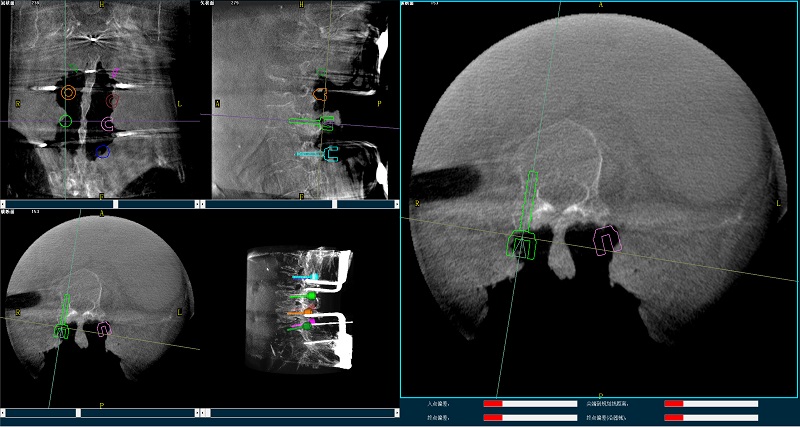

三维图像

(2)使用普爱医疗平板三维C形臂扫描患者,得到术中三维图像并传送至骨科机器人导航系统。骨科机器人导航系统基于高清术中三维图像进行手术规划。

(4)在骨科机器人导航系统辅助下,一次性准确植入8枚椎弓根螺钉。